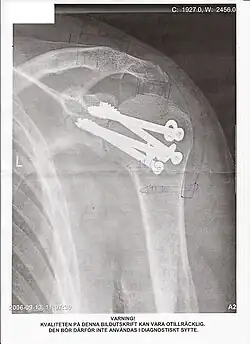

Radiographie d'une épaule ayant subi une arthrodèse